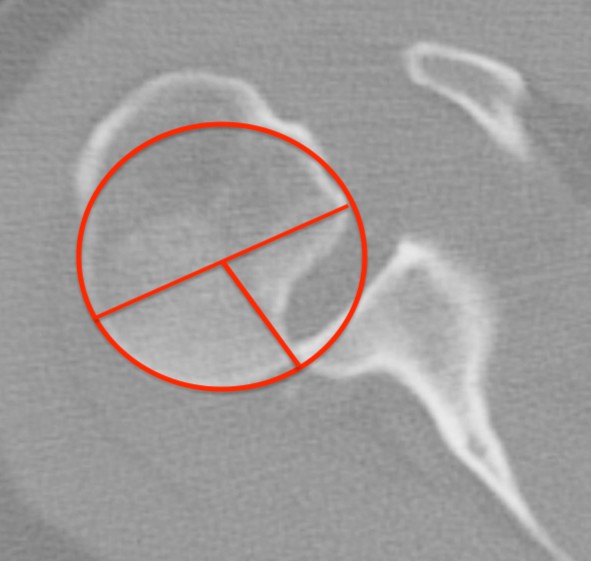

CT scan

Confirms dislocation

Reverse Hill Sachs

Humeral head defect

- caused by impaction of anterior humeral head on posterior glenoid

- intra-articular

- measured as a percentage of the articular surface

Humeral head Defect Management

| Reverse Hills Sachs < 25% | Reverse Hills Sachs 25% - 40% | Reverse Hills Sachs > 40% |